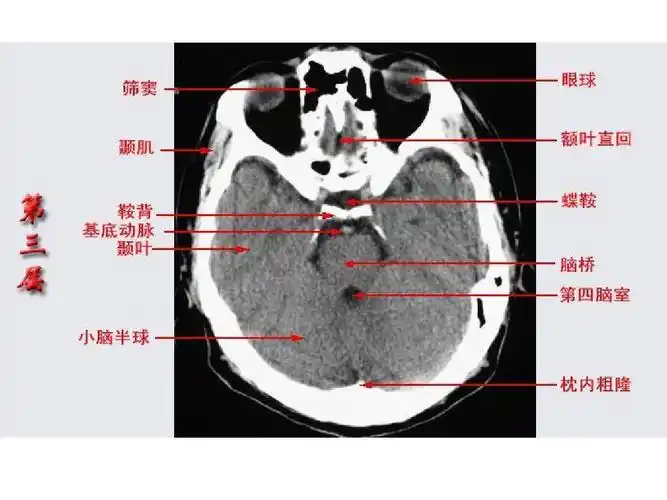

头颅ct断层解剖

10张图搞定正常头颅ct断层解剖